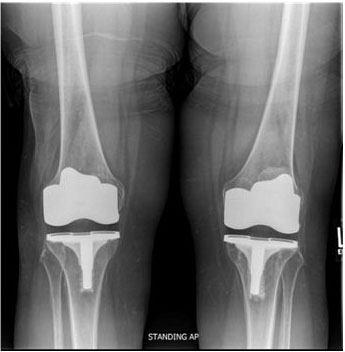

Her intra- and short-term postoperative course for the right TKA was uneventful: radiographs revealed a well fixed and aligned implant, and she had good incision healing and pain control with steady physical therapy progress. The only finding was mild right ankle burning pain at one-month post-op, considered to be routine. Her left TKA hospitalization was similarly uncomplicated; however, the patient developed post-operative redness on her left foot that progressed up her leg and persisted. At routine 12-week follow-up, the patient reported occasional discoloration and burning sensation of her left knee. Physical exam showed a diffuse erythematous/violaceous patch covering the entire lower extremity. She later developed knee pain on the right as well. Repeat radiographs revealed appropriate alignment with no signs of loosening (Figure 1).

Figure 1: Left and right anteroposterior radiographs prior to total knee arthroplasty revision surgery show appropriately aligned TKA without signs of loosening.